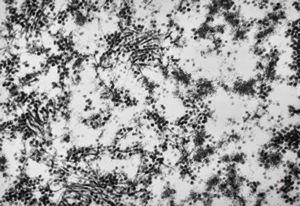

staphylococcal bacteriophage